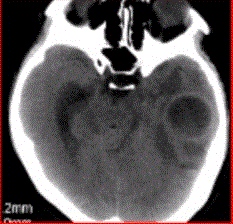

问题 患者女,26岁,头痛、低热10d余,既往有左侧慢性中耳炎病史。CT表现如下图。 关于脑脓肿的诊断要点,不正确的是

选项 A.常合并化脓性脑膜炎 B.颞叶最常见,约占40% C.多发者高达70% D.单发占70% E.病理学和影像学上可分为炎症期和脓肿形成期

答案 C